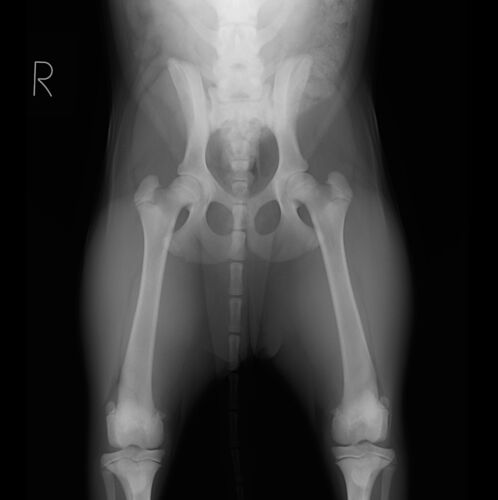

PennHIP(ペンヒップ)と股関節形成不全

病院犬(生後約4ヶ月)の股関節を、PennHIP(ペンヒップ)という特殊器具を用いたレントゲン撮影を先日実施しました。 撮影をした理由としては少し腰を振って歩いていたり、足を投げ出す様に座っていていて、股関節形成不全が疑われたからです。 下にあるのが実…